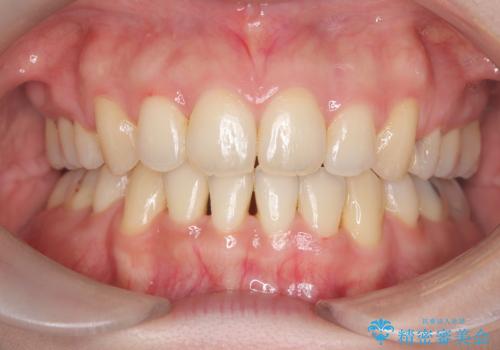

抜歯矯正により歯列のデコボコ(叢生)が改善し、前歯の突出も解消されたことで口元が下がり、すっきりとした印象となりました。

患者様にも大変ご満足いただけました。